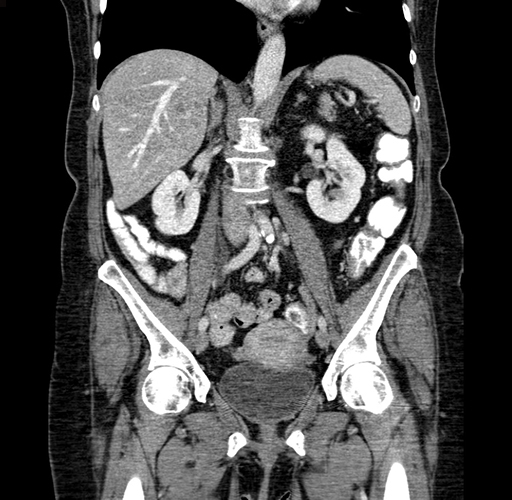

Pre-Chemo: Coronal Venous

Coronal Venous